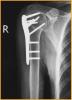

锁定板治疗老年人骨质疏松性移位的肱骨近端骨折

患者女,72岁,诊断为:肱骨近端骨折。

行肱骨近端锁定型钉板(PHILOS)固定术,手术过程:采用全麻或斜方肌阻滞麻醉,用沙滩椅体位,术中肱骨头复位后,用二至三枚克氏针临时固定保持复位,并使其余骨折块复位,然后透视确认复位质量。用5号不可吸收缝线将大小结节缝合修复,再选用适当长度的锁定钉板置于肱骨近端和肱骨干的外侧面。注意避免将钢板放置的过高以致成角螺钉的位置不合适而不能达到最佳骨接触。可用一枚非锁定螺钉固定于肱骨干上可使钢板远近端滑动调整位置。然后使用导向器上锁定螺钉使钢板和螺钉一体化。固定完成后再次透视确认无误,处理好软组织后逐层关闭切口。